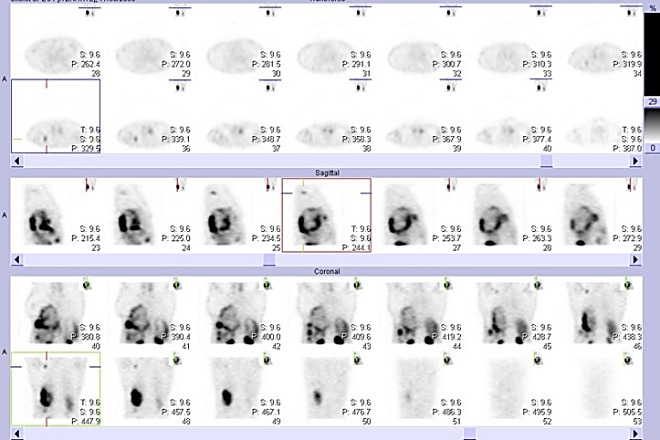

/Obr. č. 2: SPECT břicha a hrudníku 4 hod. po aplikaci

OctreoScanu.

Horní 2 řady: transverzální řezy, prostřední řada: sagitální řezy, dolní 2 řady: koronární řezy/